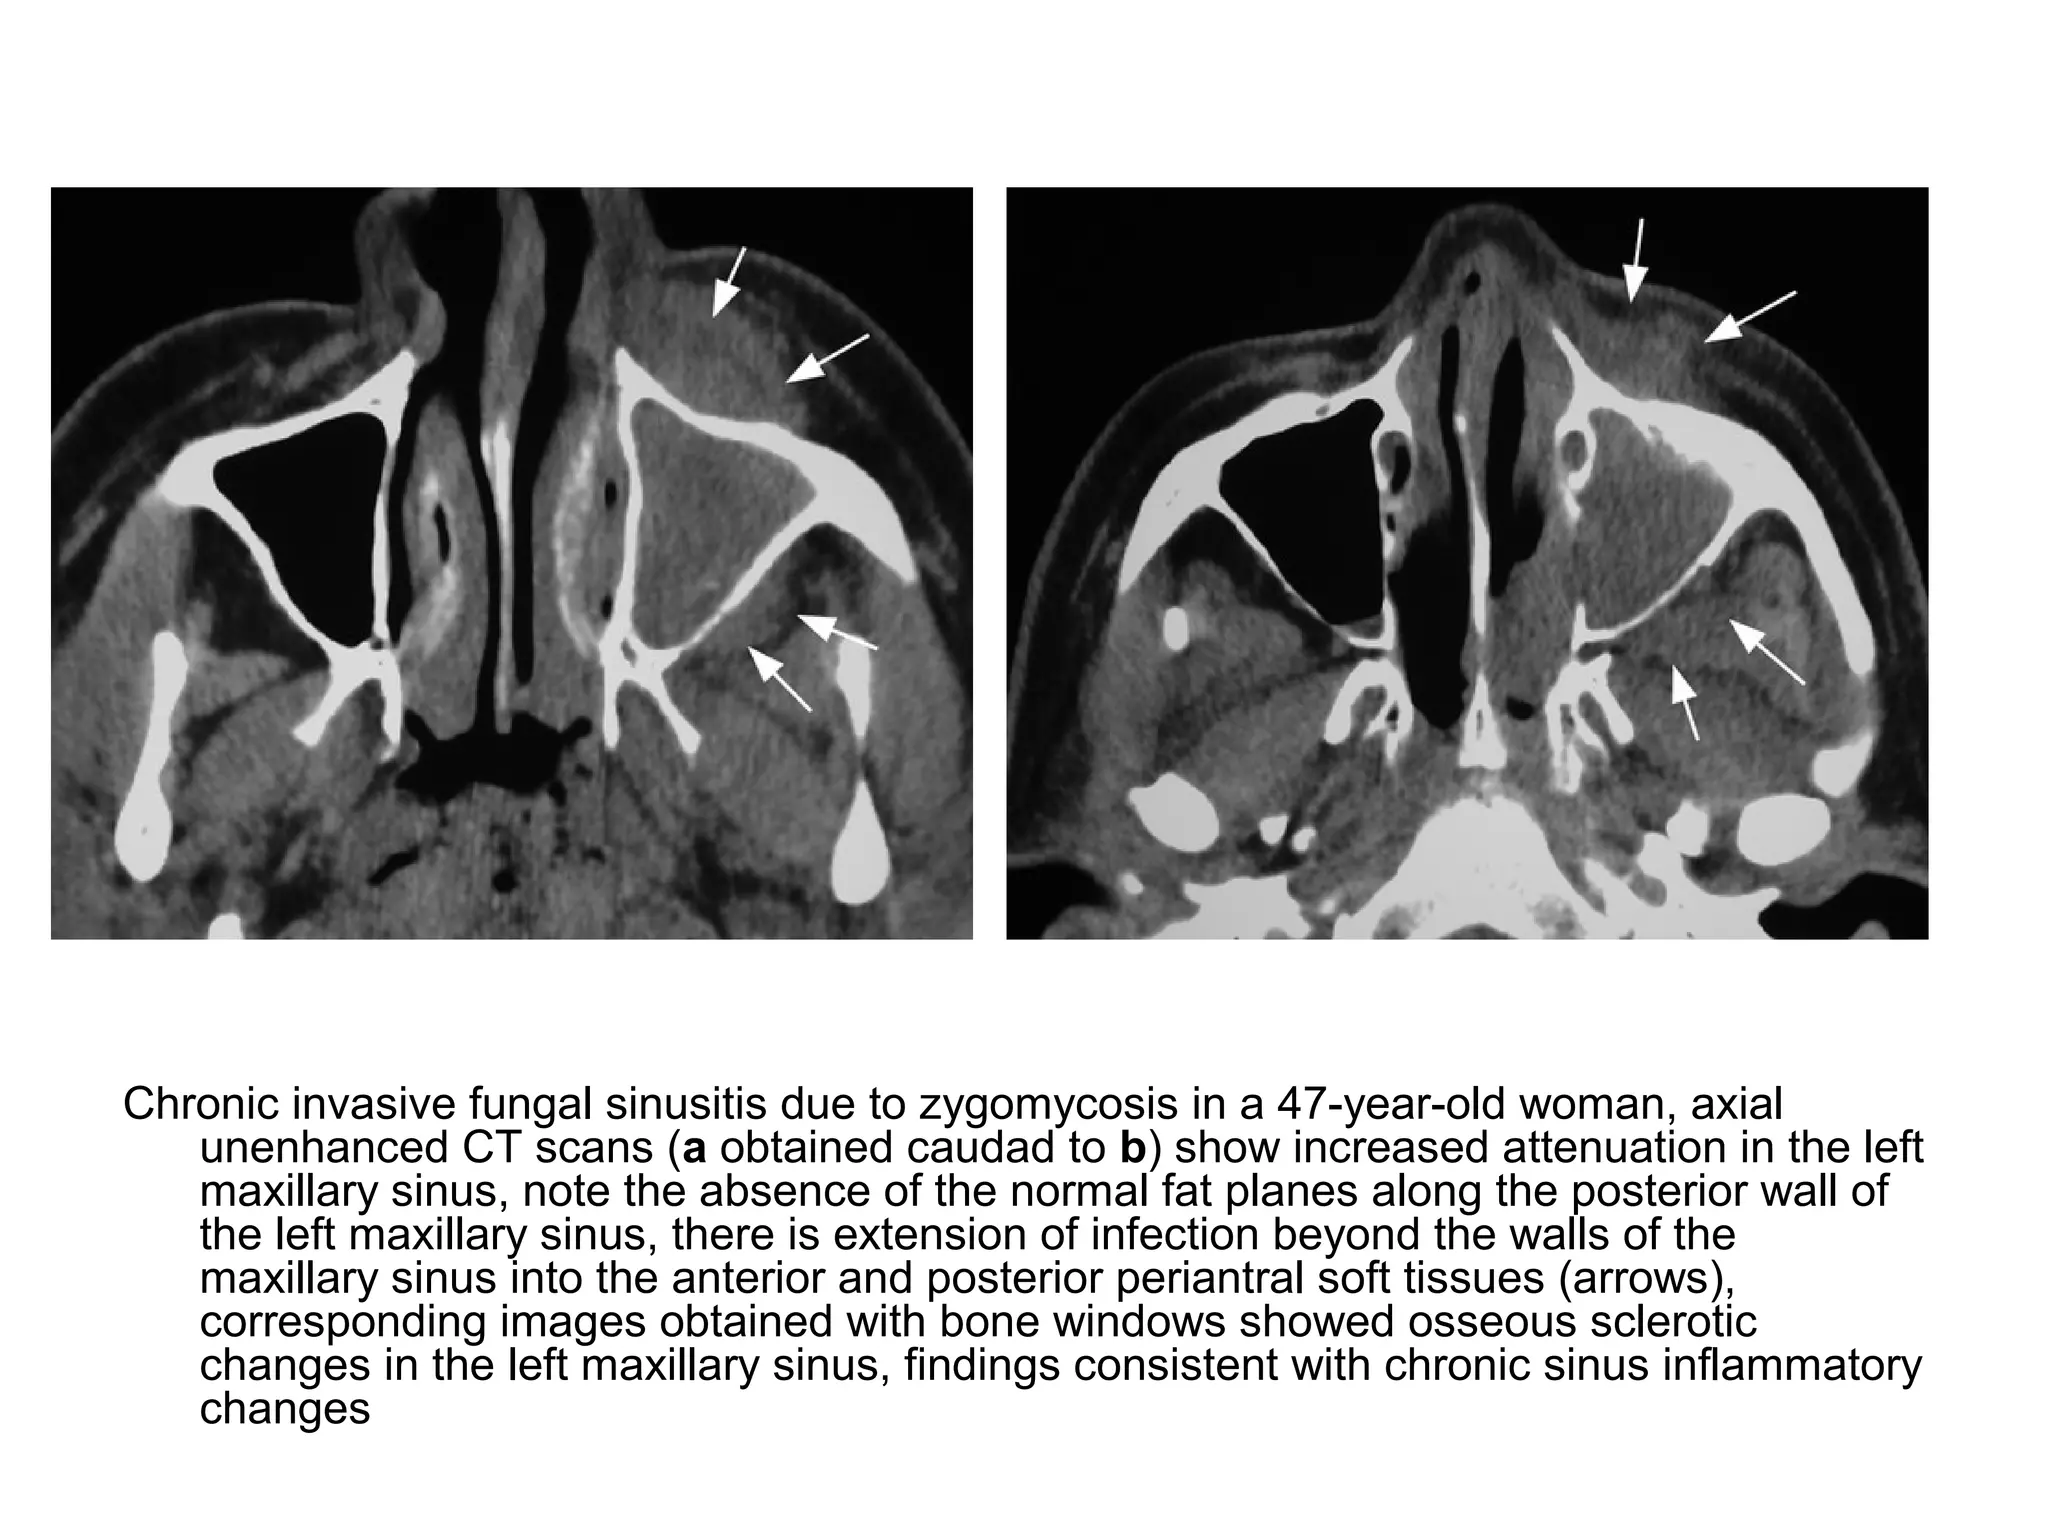

Chronic invasive fungal sinusitis due to zygomycosis in a 47-year-old woman, axial

unenhanced CT scans (a obtained caudad to b) show increased attenuation in the left

maxillary sinus, note the absence of the normal fat planes along the posterior wall of

the left maxillary sinus, there is extension of infection beyond the walls of the

maxillary sinus into the anterior and posterior periantral soft tissues (arrows),

corresponding images obtained with bone windows showed osseous sclerotic

changes in the left maxillary sinus, findings consistent with chronic sinus inflammatory

changes